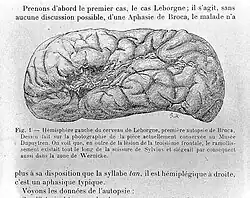

In 1861, Broca visited a patient in the Bicêtre Hospital named Louis Victor Leborgne, who had a 21-year progressive loss of speech and paralysis but not a loss of comprehension nor mental function. He was nicknamed "Tan" due to his inability to clearly speak any words other than "tan" (pronounced /tɑ̃/, as in the French word temps, "time").[68][69][66][70] Leborgne died several days later due to an uncontrolled infection and resultant gangrene, Broca performed an autopsy, hoping to find a physical explanation for Leborgne's disability.[71] He determined that, as predicted, Leborgne did in fact have a lesion in the frontal lobe in one of the cerebral hemispheres, which in this case turned out to be the left. From a comparative progression of Leborgne's loss of speech and motor movement, the area of the brain important for speech production was determined to lie within the third convolution of the left frontal lobe, next to the lateral sulcus.[72][73] One day after Tan's death Broca presented his findings to the anthropological society.[74]

A second case after Leborgne is what solidified Broca's beliefs that human speech function was localized. Lazare Lelong was an 84-year-old grounds worker who was being treated at Bicêtre for dementia. He had also lost the ability to speak other than five simple, meaningful words – these included his own name, "yes", "no", "always" as well as the number "three".[75] After his death his brain was also autopsied. Broca found a lesion that encompassed much the same area as had been affected in Leborgne's brain. This finding concluded that a specific area controlled one's ability to produce meaningful sounds, and when it is affected, one can lose their capability to communicate.[69] For the next two years, Broca went on to find autopsy evidence from twelve more cases in support of the localization of articulated language.[66][70]

Broca published his findings from the autopsies of the twelve patients in his paper "Localization of Speech in the Third Left Frontal Convolution" in 1865. His work inspired others to perform careful autopsies with the aim of linking more brain regions to sensory and motor functions. Although history credits this discovery to Broca, another French neurologist, Marc Dax, had made similar observations a generation earlier. Based on his work with approximately forty patients and subjects from other papers, Dax presented his findings at an 1836 conference of southern France physicians in Montpellier.[76][n 8] Dax died soon after this presentation and it was not reported or published until after Broca made his initial findings.[77] Accordingly, Dax's and Broca's conclusions that the left frontal lobe is essential for producing language are considered to be independent.[78][77]

However, the brains of Leborgne and Lelong had been preserved whole; Broca had never sliced them to reveal the other damaged structures beneath. Over 100 years later Nina Dronkers, an American cognitive neuroscientist, obtained permission to re-examine these brains using modern MRI technology. This imaging resulted in virtual slices of the historic brains and revealed that these patients had sustained much more damage to the brain than Broca could have known from just studying the outer surface. Their lesions extended to deeper layers beyond the left frontal lobe, including portions of insular cortex and critical white matter pathways below the cortex. This work was published in a peer-reviewed article, and has been cited.[79]

The brains of many of Broca's aphasic patients are still preserved and available for viewing on a limited basis in the special collections of the Pierre-and-Marie-Curie University (UPMC) in Paris. The collection was formerly displayed in the Musée Dupuytren. His collection of casts is in the Musée d'Anatomie Delmas-Orfila-Rouvière. Broca presented his study on Leborgne in 1861 in the Bulletin of the Société Anatomique.[66][70]